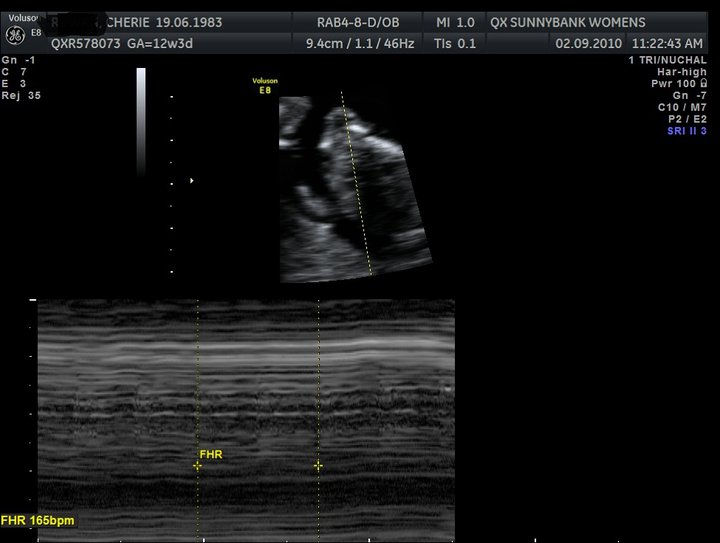

Took MW 4 ever 2 get a perfect hearing of babies heart beating as baby is sooo far back.

Babies heart rate is 130bpm